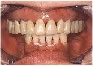

下あごの左右の奥がなくなってしまった方です。

保険で義歯をつくりましたが見た目にも機能的にも満足がいきませんでしたのでインプラントをすることを決意されました。